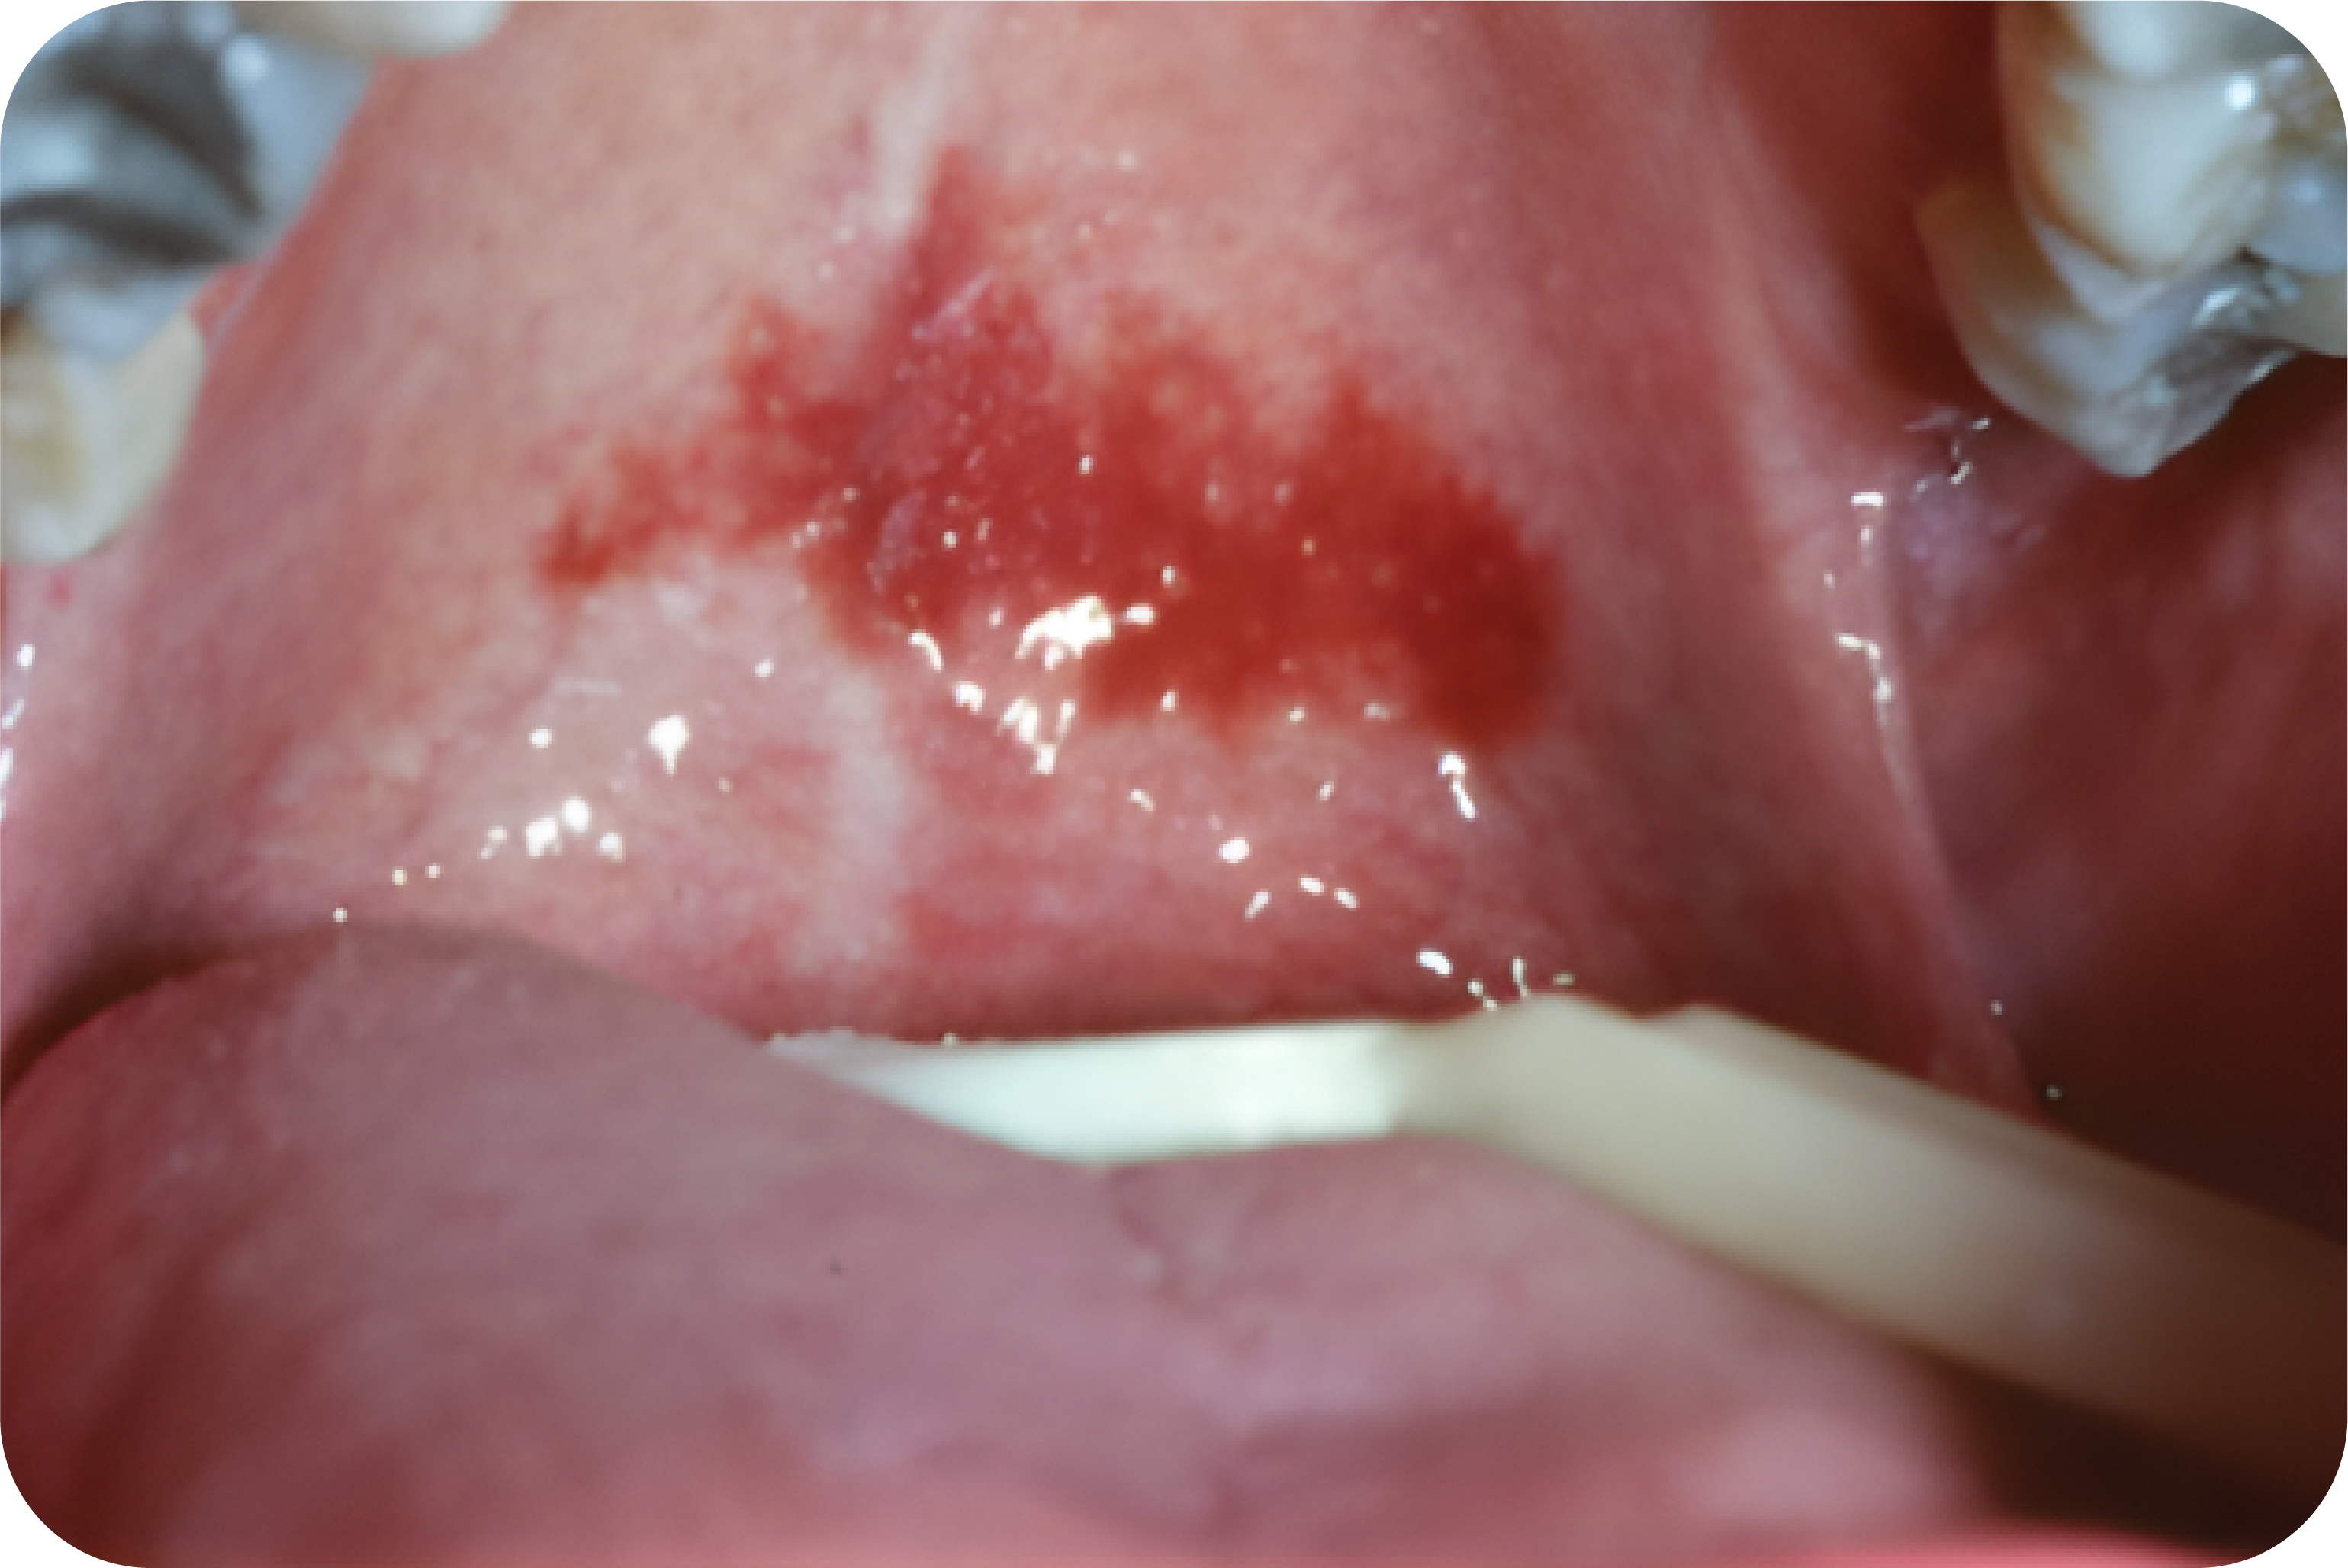

Oral Leukoplakia

Etiologi

Etiologi lesi ini dijelaskan beberapa penulis menyebutkan hubungan antara leukoplakia dan tembakau, alkohol, sanguinaria, radi

asi ultraviolet, trauma, mengunyah sirih, faktor genetik, dan mikroorganis

Gejala Klinis

Secara klinis bermanifestasi sebagai plak putih yang ireversibel, tidak dapat dikikis, dan sedikit terangkat yang mungkin tampak keriput, kasar hingga “kering atau pecah-pecah”.

Lesi ini dibagi menjadi tipe homogen atau non-homogen. Jenis homogen memiliki permukaan keputihan yang teratur dan halus dan margin yang jelas. Bentuk leukoplakia non-homogen terdiri dari bagian eritematosa (eritroleukoplakia atau tipe berbintik) atau komponen eksofitik nodular, erosif, ulserasi, atau verukosa.

Pada tipe berbintik lesi didominasi warna putih. Leukoplakia verukosa memiliki permukaan yang meninggi, proliferatif, atau bergelombang, dan tipe nodular mengembangkan pembesaran polipoid kecil atau sebagian besar bercak putih

Oral leukoplakia umumnya terlokalisir atau meluas pada mukosa bukal, vermilion bibir, dan gingiva.